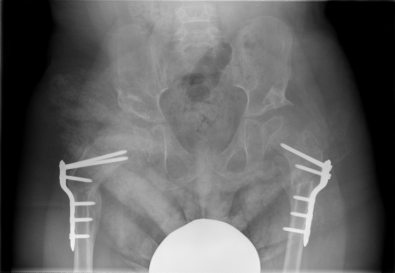

Πρόσφατες ιατρικές εξελίξεις συνιστούν την ταυτόχρονη διόρθωση όλων των παραμορφώσεων σε ασθενείς με εγκεφαλική παράλυση κατά τη διάρκεια μιας επέμβασης. Αυτή η μέθοδος έχει πολλαπλά μακροπρόθεσμα οφέλη σε σύγκριση με άλλες επεμβάσεις που διορθώνουν κάθε παραμόρφωση ξεχωριστά. Όλες οι παραμορφώσεις διορθώνονται σε μία χειρουργική επέμβαση, η οποία περιλαμβάνει επεμβάσεις οστού και μαλακού ιστού χρησιμοποιώντας ελάχιστα παρεμβατικές τεχνικές και σταθερότητα που επιτρέπει γρήγορη κινητοποίηση. Προεγχειρητικά, όλοι οι ασθενείς αξιολογούνται από κοινού με τους φυσιοθεραπευτές τους και, αν είναι δυνατόν, ανάλογα με την κινητικότητα του παιδιού, πραγματοποιείται ανάλυση βάδισης. Μετεγχειρητικά, διαμορφώνεται ένα στοχευμένο πρόγραμμα αποκατάστασης για τον συγκεκριμένο ασθενή.

Αυτό το παιδί υποβλήθηκε σε αμφοτερόπλευρη χειρουργική στα ισχία και χαλάρωση μαλακών μορίων από τον Δρ Ζένιο σε μια μόνο επέμβαση